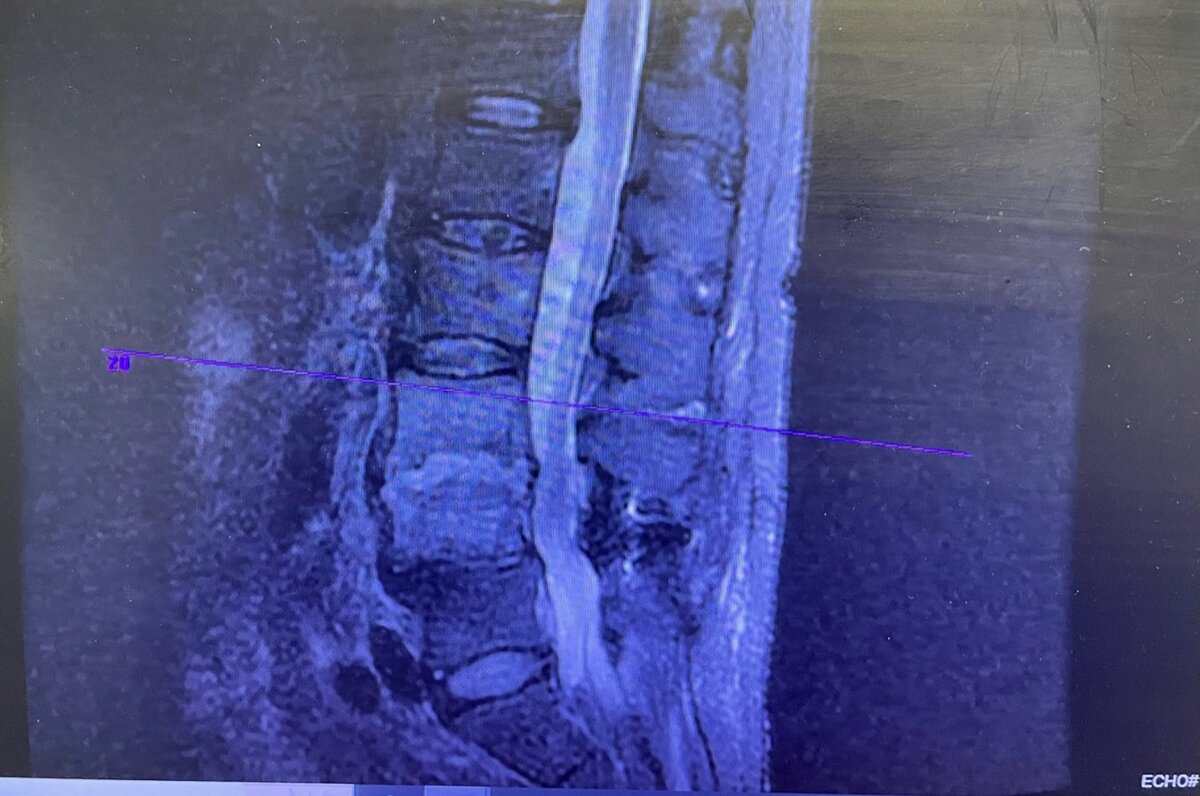

So you’re saying I shouldn’t have chosen the option with the lowest pro fee?Just add to the fusion. Already ruined his spine. 🙂

Nevro when it doesn't work. Fusion after Nevro.

Abbott after fusion.